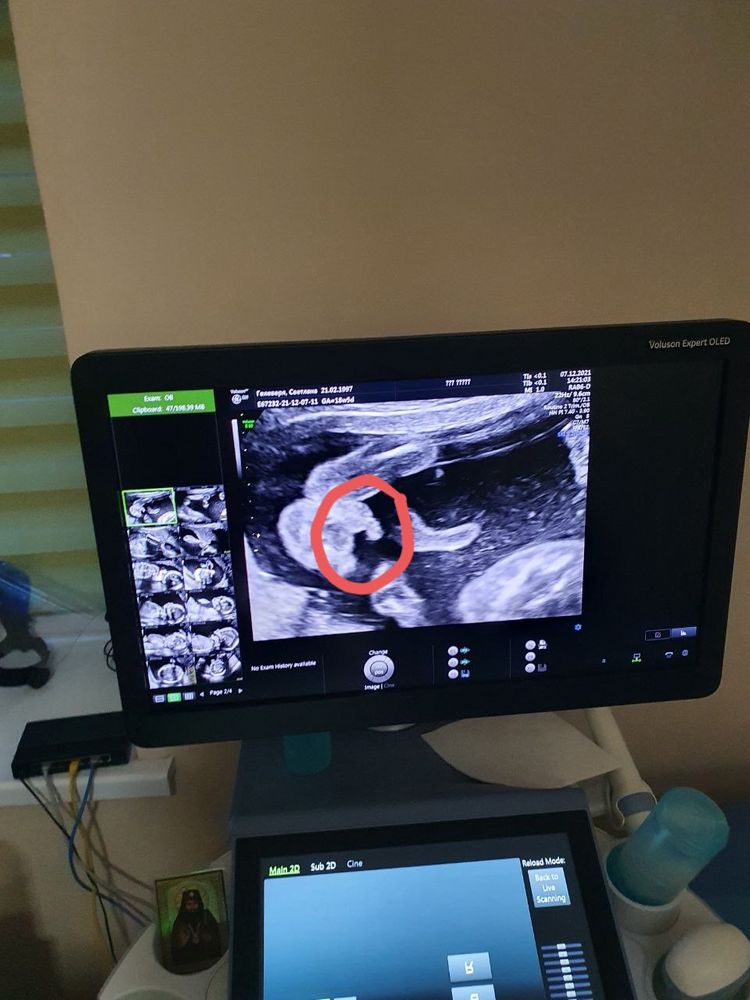

Светлана , это у вас какая неделя по снимку ?))

Герман Верин, 18.6